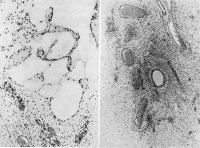

Die histologische Untersuchung ergab ein Lymphangiofibrom. Es fanden sich weite, verschieden geformte Hohlräume mit einer flachen, einschichtigen Zelllage (Endothel) ausgekleidet. Im lockeren, faserigen Zwischengewebe reichlich uniforme Zellen. In kompakteren Abschnitten des Tumors perivaskulär Anhäufungen fibrozytärer kollagenfasrigen Gewebes sowie eine Verdichtung kleiner Zellen (Abbildung 2).